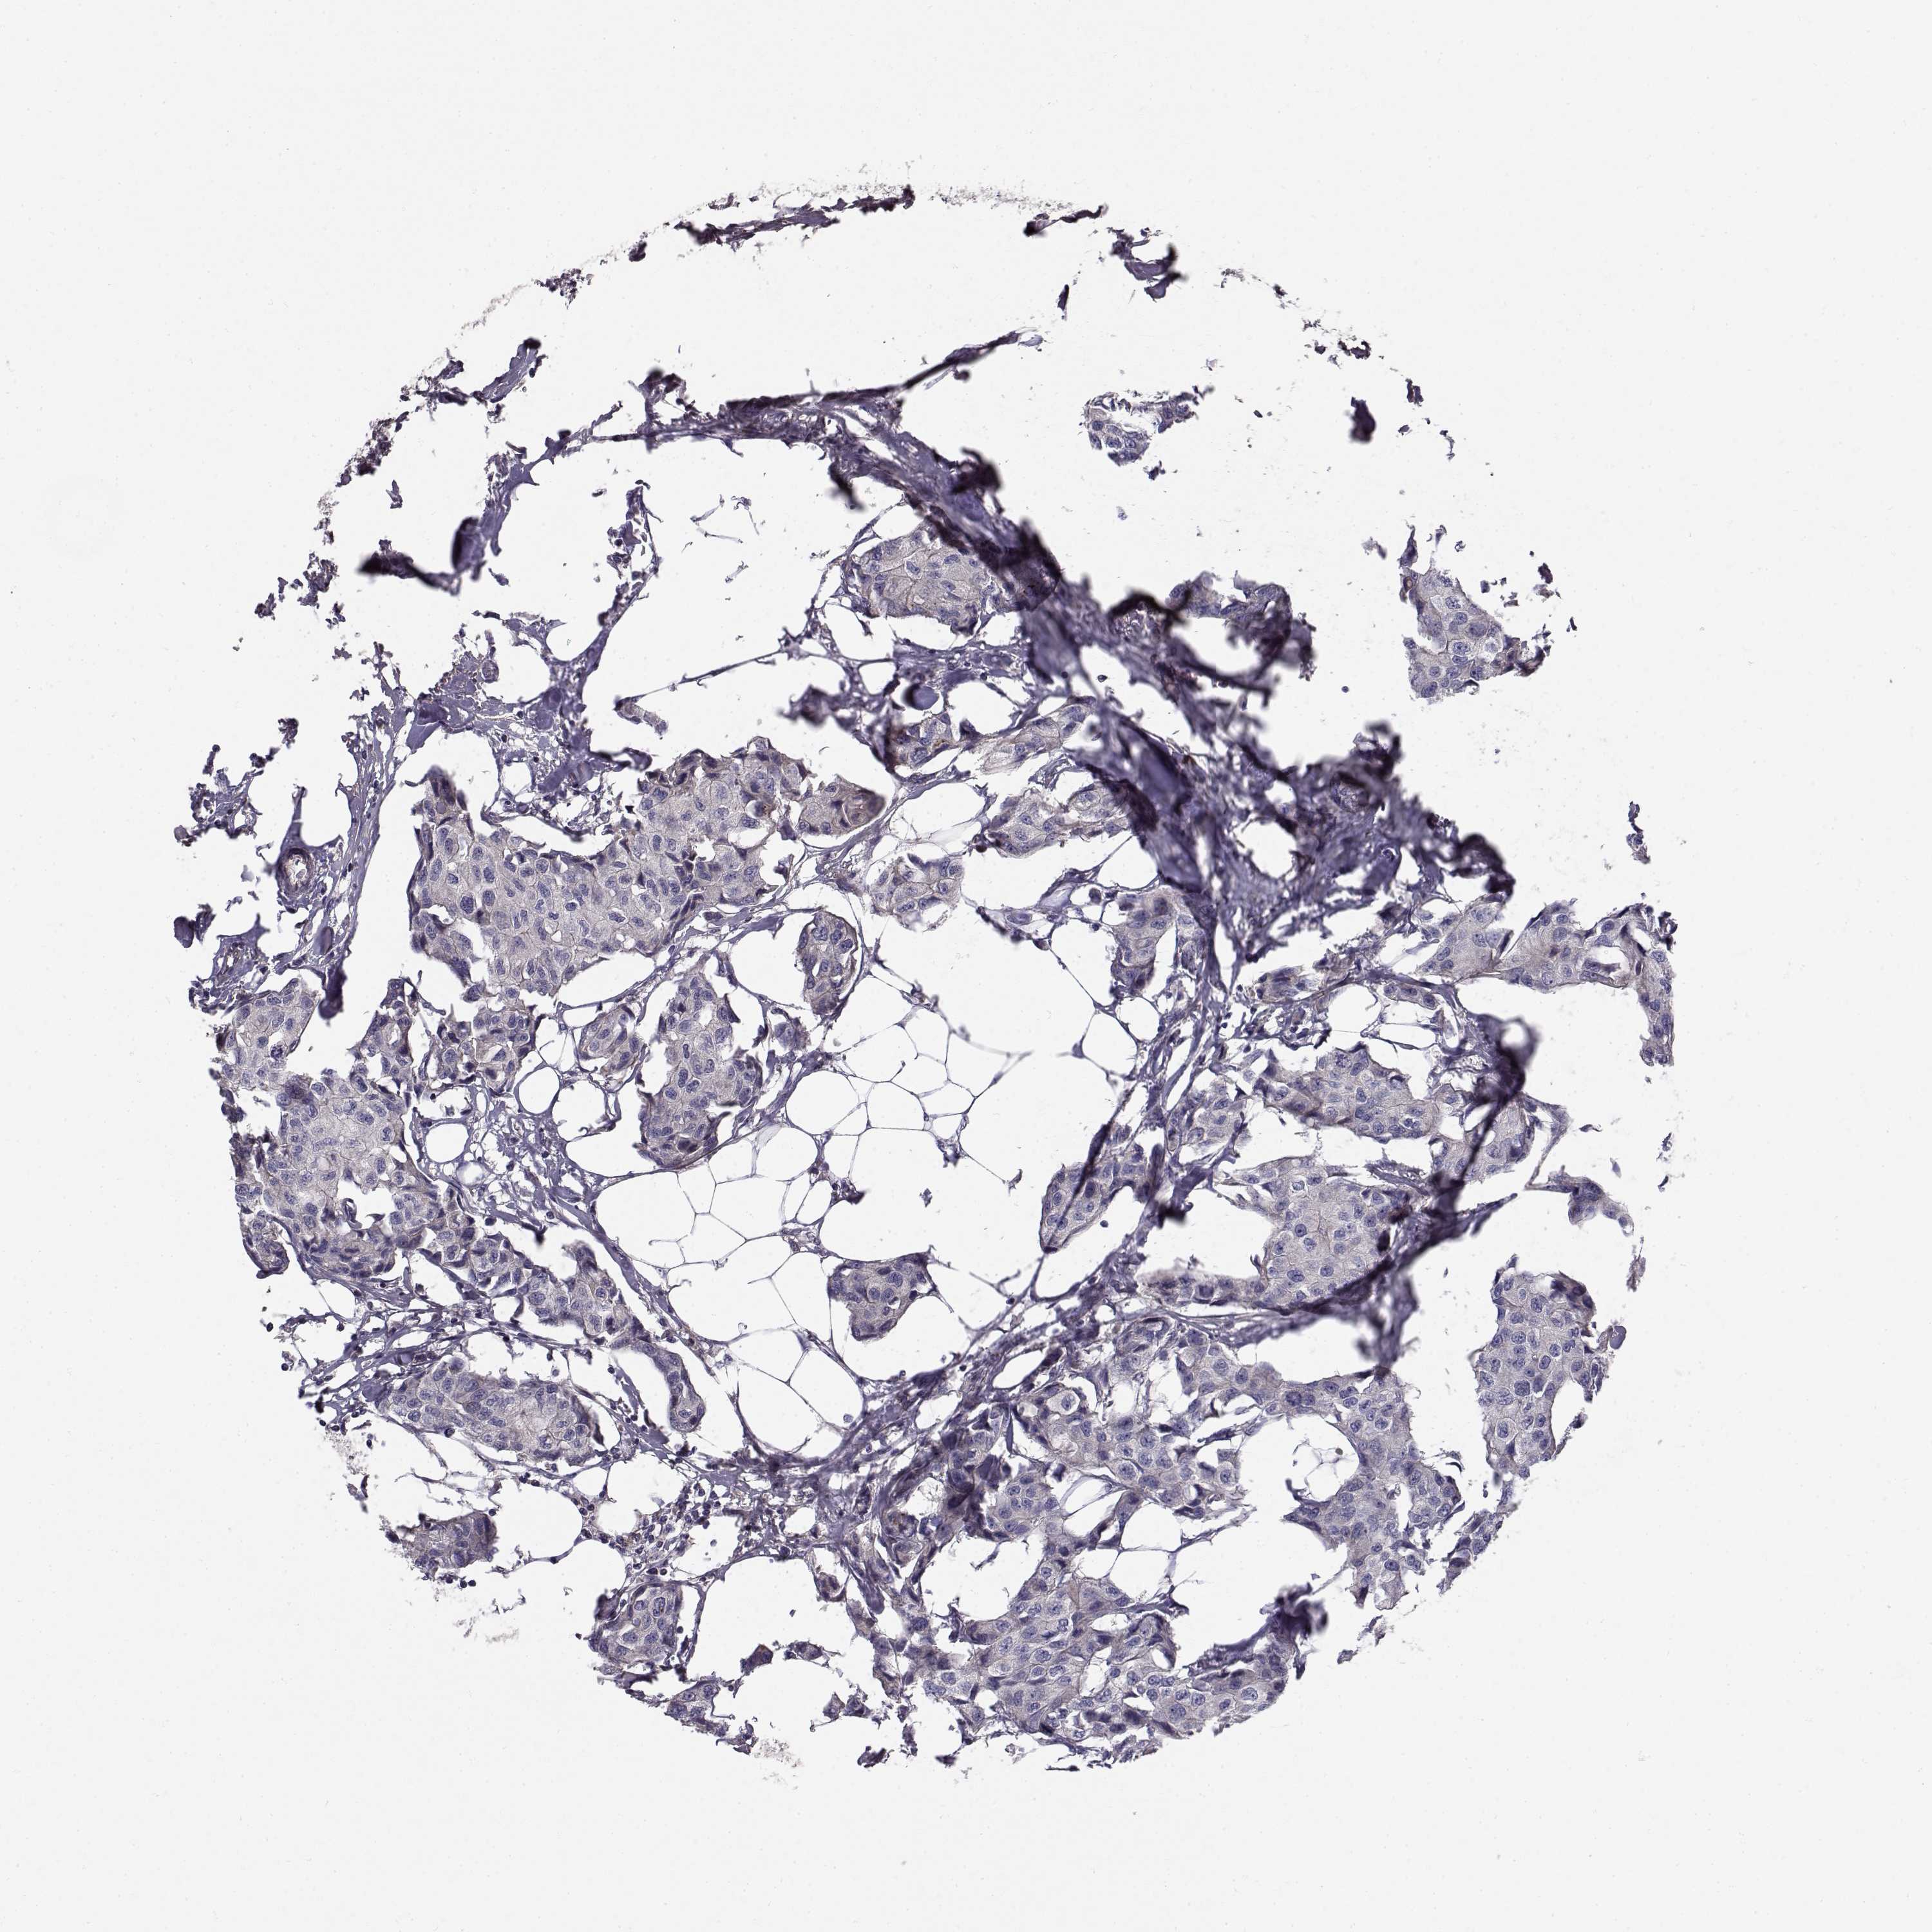

CANCER BREAST CANCER Show tissue menu

BRCA TCGA BRCA VALIDATION PROTEIN EXPRESSION